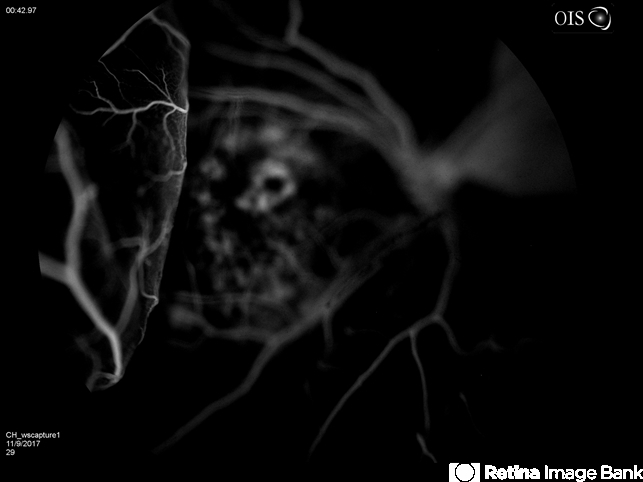

- hemorrhagic choroidal detachment, subretinal hemorrhage, choroidal neovascularization (CNV)

- 86-year-old female with hemorrhagic choroidals, choroidal neovascularization and a large subretinal hemorrhage. Vision 20/CF. Treated with intraocular injections.